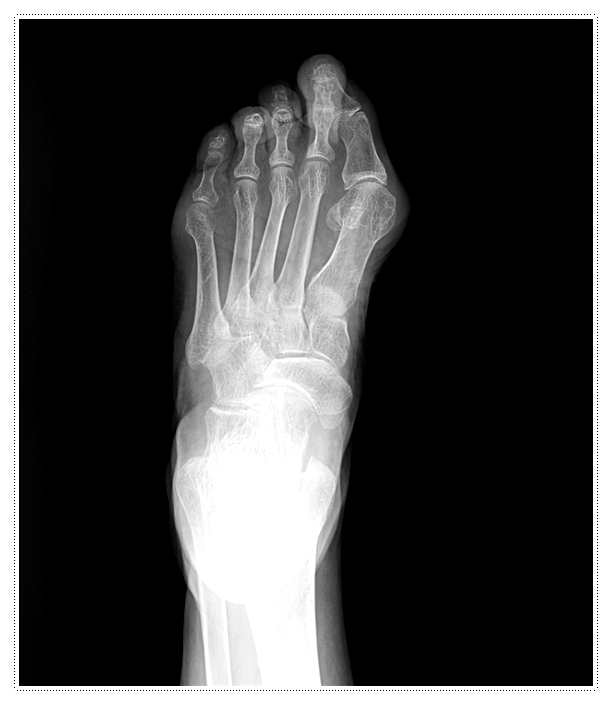

이러한 증상은 신경 주변의 압박으로 인해 신경이 두꺼워지는 ‘지간신경종’ 증상일 가능성이 높은데요.

주로 하이힐을 신거나 볼이 좁은 신발을 자주 착용하는 것이 원인으로 알려져 있습니다.

그 이유는 발바닥 앞쪽에 체중이 과도하게 집중되면서 부담이 커지기 때문입니다.